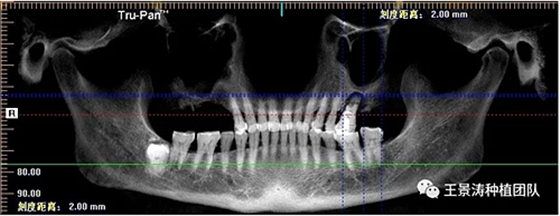

左側(cè)下頜第二磨牙及右側(cè)下頜第一磨牙同時(shí)即刻種植病例?;颊吣贻p女性,無系統(tǒng)性疾病。37及46殘冠及殘根,且46劈裂,無法冠修復(fù),必須拔除。37根尖慢性炎癥,大量肉芽組織存在,46根分叉較高,根分叉骨質(zhì)尚可。CBCT示:根尖骨質(zhì)至下牙槽神經(jīng)管距離可滿足種植體的初期穩(wěn)定性,遂考慮即刻種植,并在種植體周邊填入骨粉并覆蓋骨膜,雙側(cè)的種植體初期穩(wěn)定性相差無幾,但考慮到37根尖慢性炎癥較大,遂給予埋入式種植。

患者左側(cè)16慢性根尖周炎,17缺失。16根尖炎癥距上頜竇底較近,需內(nèi)提升,但是因?yàn)閮?nèi)提升后骨質(zhì)較薄所致植入深度過深,埋入式植入。17非埋入式種植。后期效果均可。